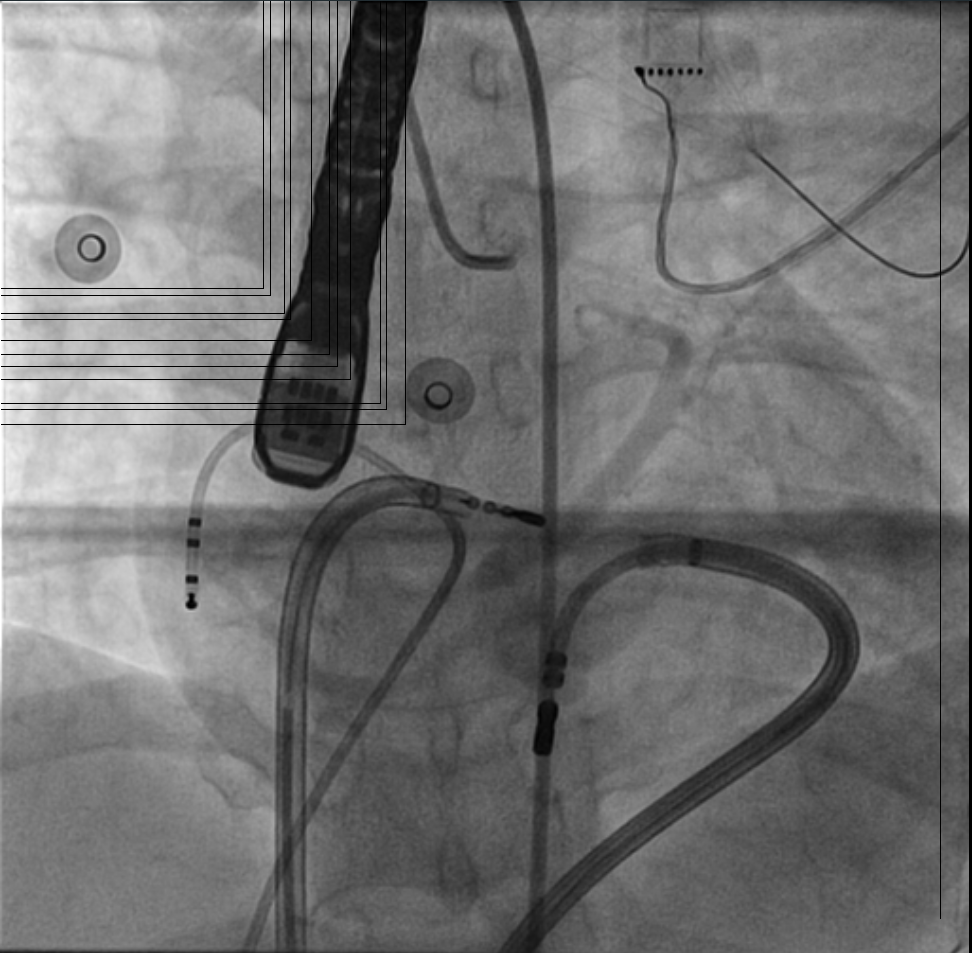

Non annular location of AP

fig2.jpg

fig3.jpg